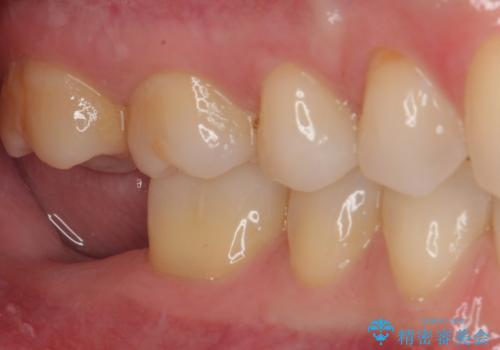

- 奥歯が抜歯となり、インプラント治療を希望して来院された患者様です。

来院時には抜歯して1ヶ月ほど経過していたとのことで、3次元レントゲンよりインプラントの早期埋入が可能と診断されました。

インプラント埋入と同時に仮歯を装着するために、事前に仮歯を用意し、速やかにインプラント埋入を行うこととしました。

抜歯された骨の穴は、インプラント埋入時にはまだ大きな窩洞となっていましたが、径の大きいワイドインプラントを選択することで、埋入時に十分な安定を獲得することができました。

後方には欠損が残っていたため、補填材を填入しました。

術後にインプラントが骨から脱落することがありますが、特筆するトラブルなどなく、最短の3ヶ月で治療を終えることができました。